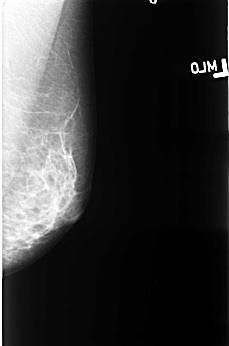

B_3403_1.RIGHT_CC

FILE: B_3403_1.RIGHT_CC.OVERLAY

TOTAL_ABNORMALITIES 1

ABNORMALITY 1

LESION_TYPE MASS SHAPE IRREGULAR MARGINS OBSCURED-ILL_DEFINED

ASSESSMENT 4

SUBTLETY 2

PATHOLOGY MALIGNANT

TOTAL_OUTLINES 1

BOUNDARY